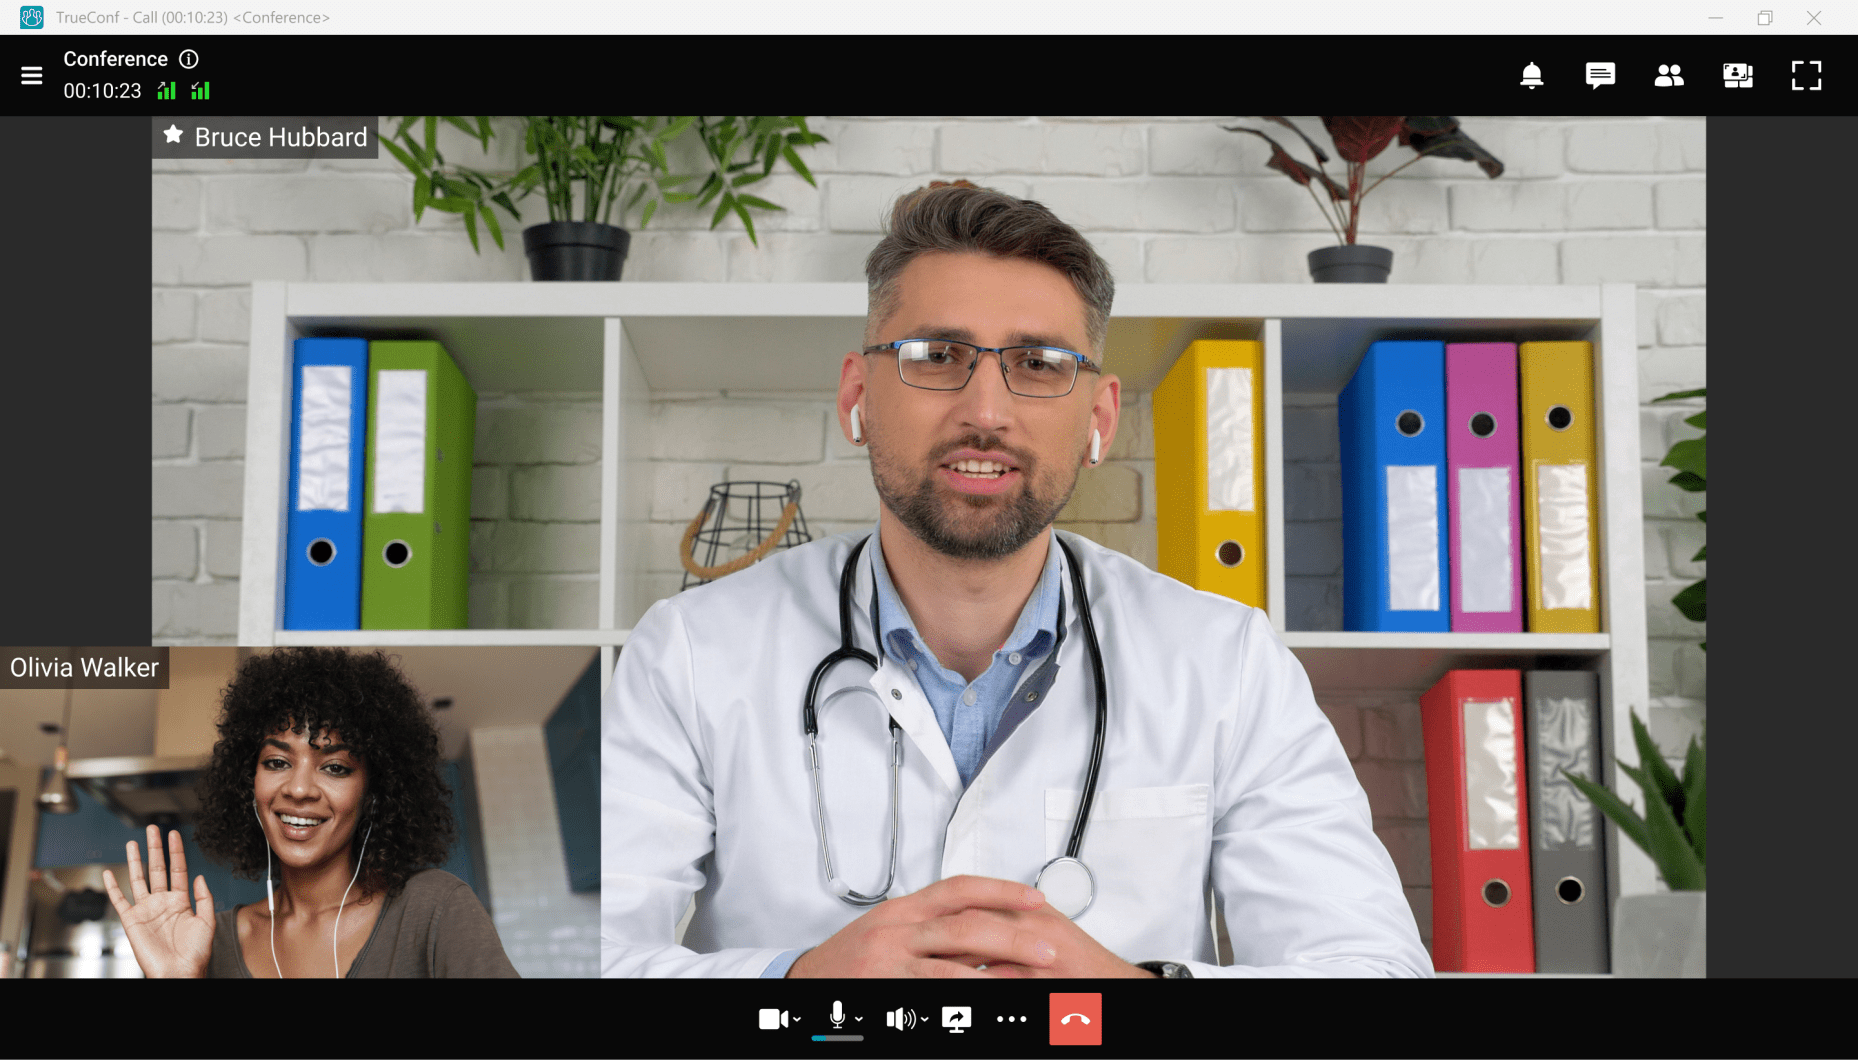

TrueConf Server

UltraHD meeting server with powerful integration and collaboration capabilities.